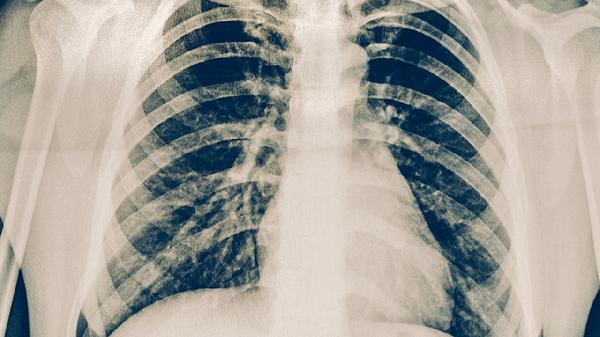

部分患者可能面临治疗失败风险。耐药谱更广的广泛耐药结核病治愈率显著降低,合并糖尿病或免疫功能低下者预后较差。治疗过程中可能出现肝肾功能损害、听力下降等药物不良反应,需及时调整方案。中断治疗会导致耐药性进一步加重,甚至发展为广泛耐药结核病。对于肺部病灶广泛破坏者,可能需要联合外科手术干预。

建议确诊后立即在结核病定点医疗机构接受规范治疗,治疗期间避免与他人密切接触。保持居室通风,佩戴口罩可降低传播风险。定期复查胸部CT和肝功能,出现视力异常、关节疼痛等不良反应时需及时就医。完成全程治疗后仍需随访2年以确认无复发。